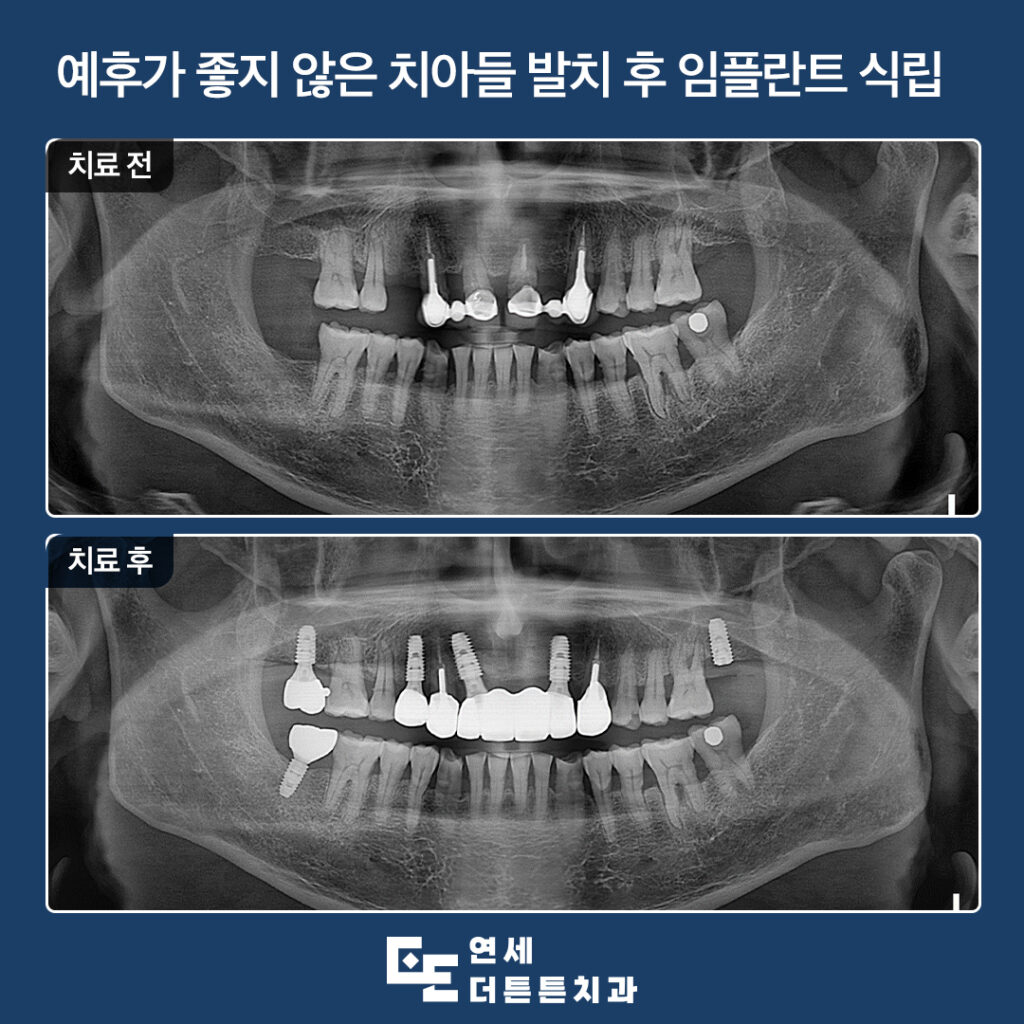

오늘은 예후가 좋지 않은

기존의 자연치아들을 발치하고

도봉동치과 잘하는곳에서 임플란트 식립을

진행하신 환자분을 소개해 드리려고 합니다.

환자분께서는 좋지 않은 치아들을

하나둘씩 빼다 보니 치아가 없는 부위도

많고 씌워두었던 앞니들이 흔들리신다며

내원해 주셨습니다.

먼저 식립한 임플란트는

최종 보철물을 마무리하고

왼쪽 위 어금니는 기존 잇몸뼈와

충분히 융합될 수 있도록 기간을 기다려준 뒤

최종 보철물을 진행할 예정입니다.